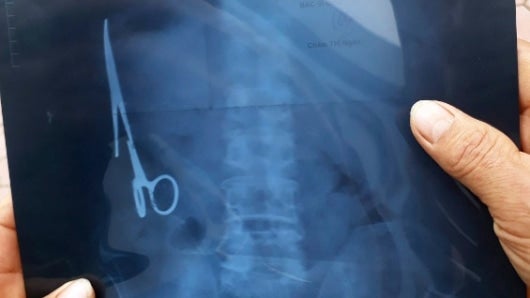

Un vietnamita ha vivido 18 años con unas tijeras que los médicos se olvidaron en su estómago y de cuya presencia nadie se había dado cuenta hasta el mes pasado, cuando sufrió un accidente de tráfico y le hicieron una radiografía.

La intervención quirúrgica para retirar el instrumento médico de 15 centímetros de largo se realizó el sábado pasado en un hospital de la provincia de Thai Nguyen, en el norte de Vietnam, y duró unas tres horas.

Las tijeras se encontraban oxidadas, en la parte izquierda del estómago, según los doctores que el intervinieron citados por el medio vietnamita Tuoi Tre.

El paciente, un hombre de 54 años, nunca había sentido molestias por la presencia de las tijeras que se olvidaron en su estómago en junio de 1988, cuando le intervinieron en el Hospital General Bac Kan por otro accidente de tráfico.